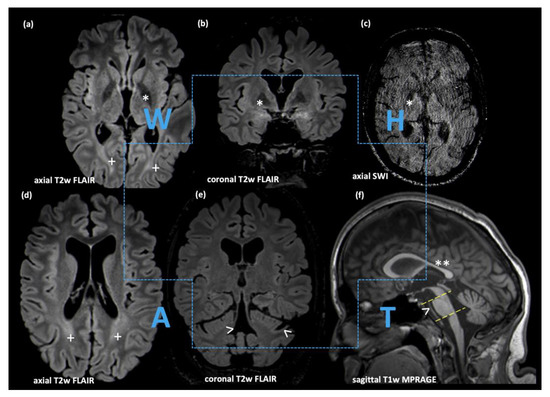

3.1. Case Report

3.2. Molecular Genetic Analysis